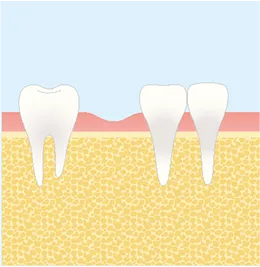

インプラント手術の流れ

インプラント治療は、一般的に「一次手術」と「二次手術」の2段階で行われます。

流れを正しく理解することは、納得して治療を受けるために大切なステップです。

FLOW01

一次オペ

(インプラント埋入)-

STEP1

麻酔

STEP2

歯ぐきの切開

STEP3

インプラント埋入

STEP4

歯ぐきの縫合